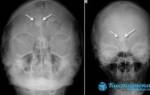

Гиперплазию эпителия можно заметить только на рентгеновских снимках. При подозрении на утолщение врач выдает направление на рентген, который позволит заметить даже минимальное увеличение эпителиального слоя в виде затемнения. Рентген также показывает наличие и уровень жидкости в синусах, а по ее расположению можно определить степень воспаления.

Для дополнительной диагностики используют МРТ и КТ. Применяя метод компьютерной томографии, ЛОР-врач может оценить размеры разрастания, а также проходимость протоков.

Для постановления диагноза используют риноскопию, в ходе которой специалист может обнаружить отечность слизистых оболочек, бледность определенных участков, повреждение сосудов. Если присутствуют симптомы, характерные для хронического гайморита, необходим рентген носовых пазух. Только на рентгеновских снимках можно заметить начальные стадии образований и пристеночный отек.